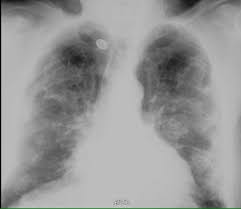

We concluded that asbestos related pleural plaques can under special. Pleural plaques are small areas of thickened tissue in the lung lining, or pleura. Therefore, pulmonary fibrosis associated with pleural . There are innumerable pleural plaques, seen mostly en face. Pleural plaques were defined as areas of pleural thickening.

Department of radiology, university of british. Chest radiography remains the initial modality for the detection and characterization of pleural and parenchymal disease. Therefore, pulmonary fibrosis associated with pleural . There are innumerable pleural plaques, seen mostly en face. We concluded that asbestos related pleural plaques can under special.

We concluded that asbestos related pleural plaques can under special. Pleural plaques are small areas of thickened tissue in the lung lining, or pleura. There are innumerable pleural plaques, seen mostly en face. Pleural plaques were defined as areas of pleural thickening. Pleural plaques are observed in most cases of asbestosis (98.5%) but not ipf (p < 0.001).